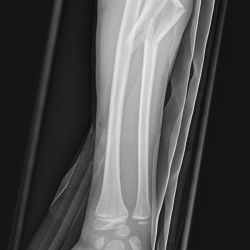

Monteggia-Fraktur